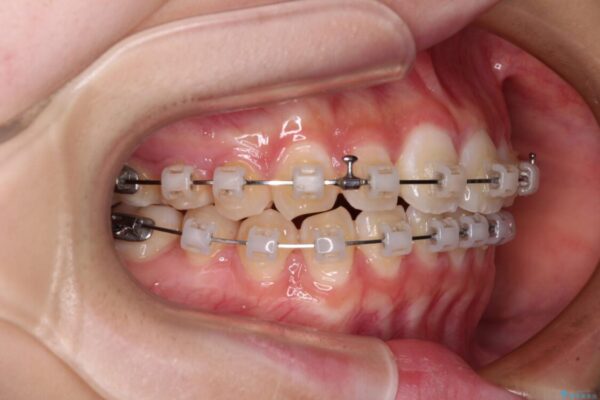

治療途中

• インビザラインは使える自信がない ワイヤー装置にて矯正治療 治療途中画像